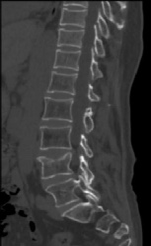

开展的CT检查项目有:全身 CT平扫和增强 检查(含头颅、颈部、胸部、腹部、盆腔、骨关节,四肢等)。

特色项目:(1)CT下肢动脉血管成像(CTA);通过增强血管成像,可清楚显示并明确动脉血管病变范围、程度和性质,如下肢动脉狭窄,闭塞等。(2)心脏冠状动脉CTA:通过增强检查,可显示多种心脏疾病,分析冠脉斑块成分及狭窄程度。(3)CT定位下穿刺活检:在CT引导下对病变部位进行穿刺,取病变组织用于病理检查,明显病变性质。常用于胸部、肝脏、肾脏、骨骼等部位。